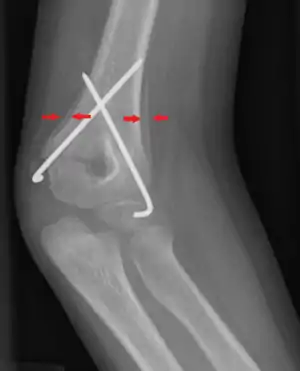

| Periosteal reaction on a healing supracondylar fracture | |

A periosteal reaction is the formation of new bone in response to injury or other stimuli of the periosteum surrounding the bone.[1] It is most often identified on X-ray films of the bones.

A periosteal reaction can result from a large number of causes, including injury and chronic irritation due to a medical condition such as hypertrophic osteopathy, bone healing in response to fracture, chronic stress injuries, subperiosteal hematomas, osteomyelitis, and cancer of the bone. It may also occur as part of thyroid acropachy, a severe sign of the autoimmune thyroid disorder Graves' disease.

The morphological appearance can be helpful in determining the cause of a periosteal reaction (for example, if other features of periostitis are present), but is usually not enough to be definitive. Diagnosis can be helped by establishing if bone formation is localized to a specific point or generalized to a broad area. The appearance of the adjacent bone will give clues as to which of these is the most likely cause.

Appearances include solid, laminated, spiculated, and the Codman triangle.[4]